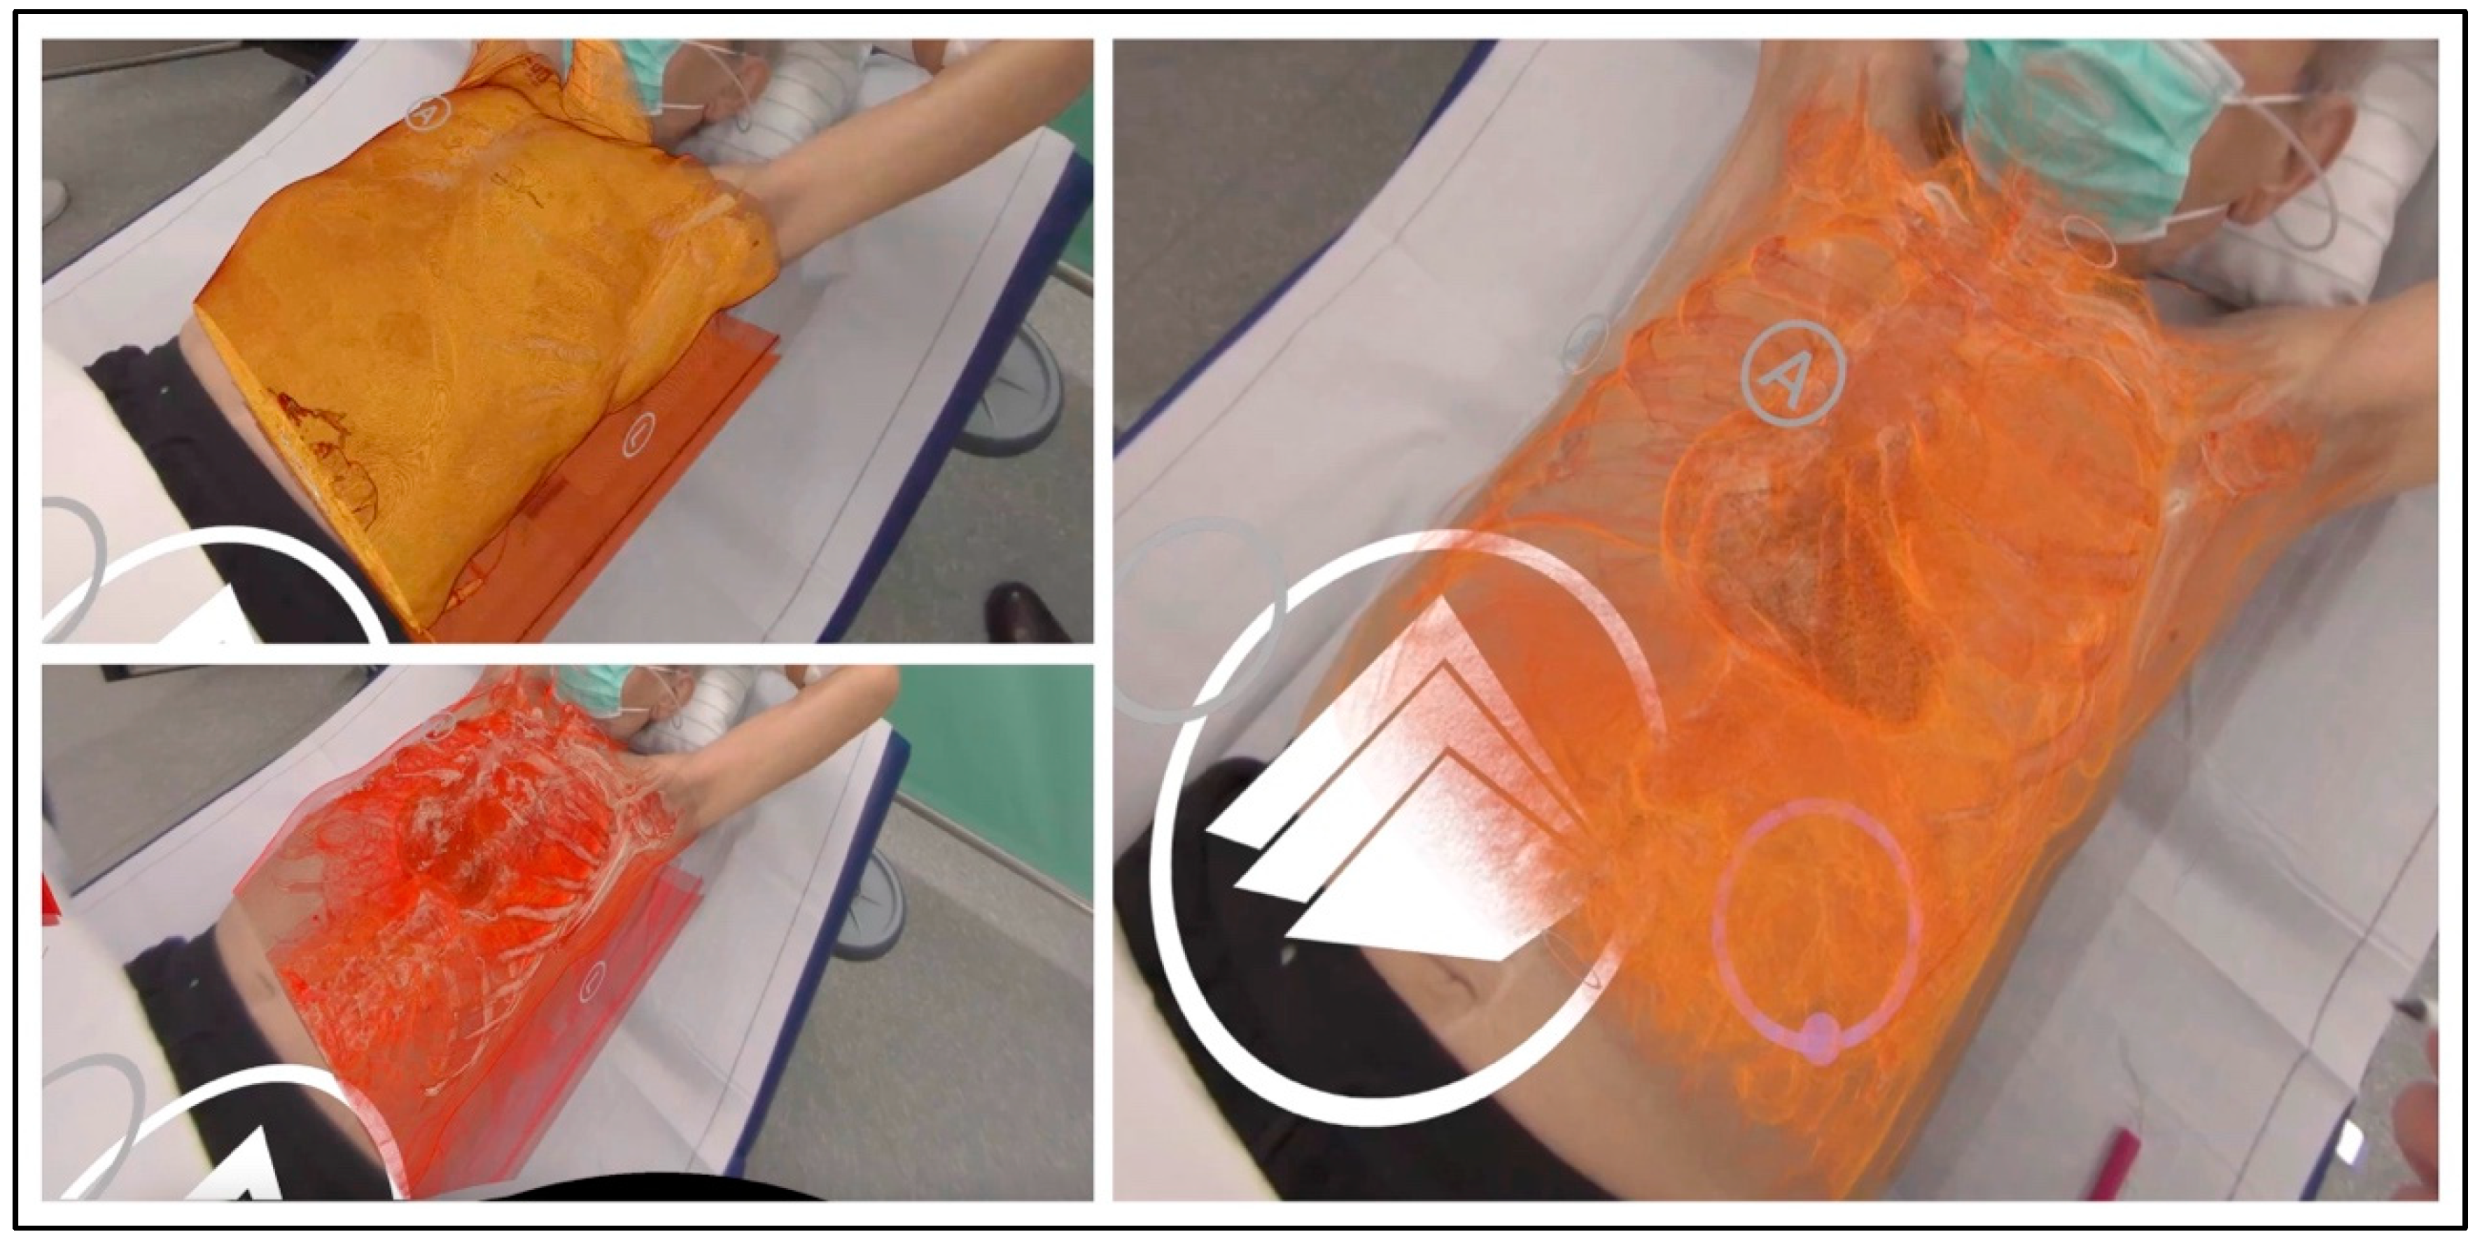

Figure 3 presents the dynamic tissue windowing and color grading during the XR examination, adjusting the intensity of skin, soft tissue, costal, and tumor visualization to comprehend the surgical assessment.